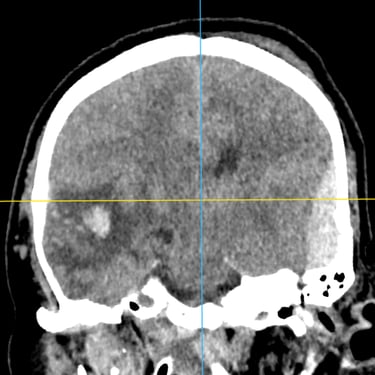

TEC Severo: Craneotomía Descompresiva Hemisférica y Evacuación de Hematoma Extradural

El traumatismo encéfalo craneano (TEC) severo es una emergencia neurológica que puede comprometer rápidamente la vida del paciente. Cuando existe edema cerebral difuso y hematomas asociados, el tratamiento quirúrgico oportuno es fundamental. La craneotomía descompresiva hemisférica derecha permite reducir la presión intracraneal y prevenir daño cerebral secundario, mientras que la craneotomía temporal izquierda con evacuación de hematoma extradural (HED) elimina el efecto de masa local. Este abordaje combinado busca preservar la perfusión cerebral, estabilizar al paciente y mejorar el pronóstico neurológico en situaciones críticas.